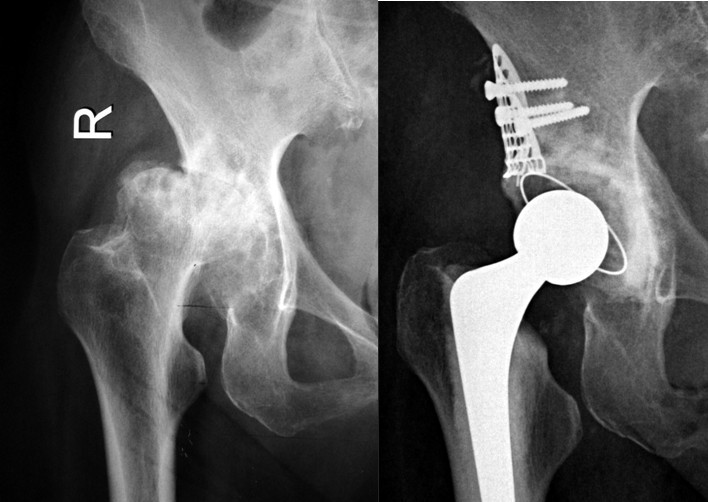

⑶Ⅲ型缺损:右髋关节置换术后骨溶解、假体无菌性松动造成髋臼巨大Ⅲ型骨缺损,行翻修术,以金属网包含髋臼上缘及髋臼内壁后,打压植骨,三代骨水泥技术全髋关节置换。